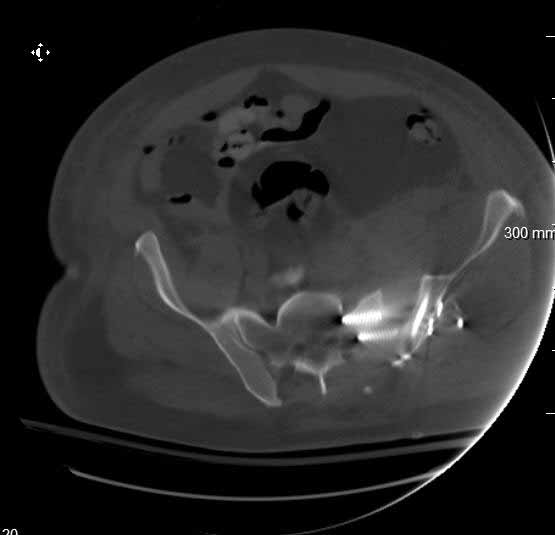

Was hemodynamic unstable at local ER, sent to our Trauma center where circumferential pelvic binder placed and pt. stabilized with fluid, blood, and rewarming. Angiography not performed. An extraperitoneal bladder disruption was found, uro elected to treat non-operatively. Initial xray (not shown) demonstrated 5-7 cm wide at symphysis and SI joint. The first image attached is of CT once binder is in place.

On post trauma day 5 the pt was taken to OR for ORIF of his iliac wing fracture and SI dislocation. The swelling/3rd spacing of fluid in the area of symphysis was profound, but quite acceptable posteriorly.